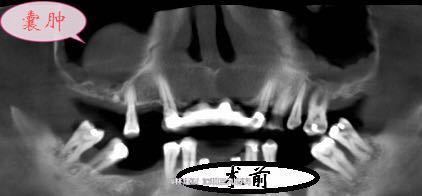

17,16,14缺失。15松动。 CT示:右侧上颌窦内中等密度影,窦嵴距约2mm。

诊断:17,16,14缺失 15牙周炎 右侧上颌窦囊肿 处理:15拔除 16行上颌窦内提升术,植入人工骨粉,盖膜。暂时保留上颌窦囊肿,择日耳鼻喉科会诊。